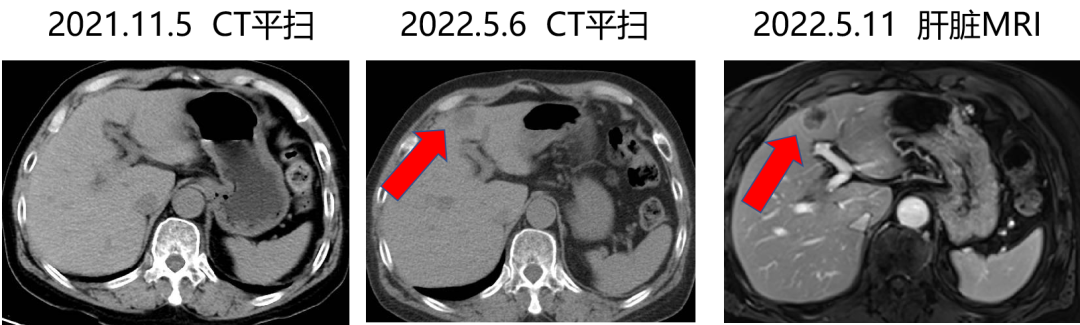

一 专家访谈 专家简介 于国华 教授 潍坊市人民医院 潍坊市肿瘤防治中心主任、潍坊市人民肿瘤医院院长、GCP机构副主任 潍坊市科技智库首席专家,省级重点学科负责人 中国临床肿瘤学会(CSCO)理事 山东省抗癌协会常务理事 潍坊市抗癌协会理事长 中国老年学学会舒缓治疗分会常务委员 中国老年学学会老年肿瘤专业委员会 中国老年学学会老年肿瘤专业委员会(CGOS)分子靶向分委会、肺癌分委会常务委员 山东省医学会肿瘤微创治疗分会副主任委员 山东省医学会姑息医学分会副主任委员 山东省肿瘤微创质量控制中心副主任委员 山东省医师协会肿瘤化疗医师分会副主任委员 山东省抗癌协会肿瘤化疗分会、肺癌分会、靶向治疗分会、心理治疗分会副主任委员 潍坊市医学会肿瘤化疗分会主任委员 潍坊市中西医结合学会肿瘤专业委员会主任委员 潍坊市肿瘤化疗专业质量控制中心主任 Q1 随着检查手段不断丰富,晚期结直肠癌的全程管理成为必然趋势。请您谈一谈我国在结直肠癌全程管理方面取得了哪些成果,未来应该朝着哪些方向努力? 我国在结直肠癌全程管理方面的进步成果,大概可以分为三个方面。 第一方面,随着医疗检测技术和诊疗理念的革新,我国早筛早治取得了良好进展。60~80年代我国检查技术相对落后,主要为粪便潜血试验展开有关肠道检查,而随着内镜技术的发展,肠镜检查逐渐普及,提高了结直肠癌早期患者的诊断率,推进了我国早诊早治的策略,使更多患者及早发现疾病并接受治疗。 第二方面,我国医疗制度具有优越性。随着我国全民医保的全面落实,“全民健康”理念的普及,就诊路径日益优化,更加快速便捷,使患者尽早获得诊断和治疗。 第三方面,国家癌症中心以及有关学协会的成立,推动了我国整体诊疗水平的不断提高。不仅为基层和各级医院搭建了良好的学习平台,推动了临床医生的再学习、再教育,也使得规范化诊疗、多学科协作(MDT)等优秀诊疗理念得以推广和实践。 第四方面,在内外科领域,药物治疗和手术治疗也是发展比较迅速。我国加速推进新药研发和医药服务创新,使更多药物尽快落地,惠及我国患者。相有关学协会积极组织形成了具有实践和指导意义的全程管理专家共识/指南,包括患者自身情况的评估、围手术期管理、治疗药物的选择、各线药物治疗方案、药物不良反应管理等。 关于结直肠癌全程管理未来的发展,需要以预防、规范化治疗和新药研发为抓手。 第一方面,预防是结直肠癌管理的第一步,未来有待在国家层面开展大规模的宣传教育,科普健康生活方式,令群众了解结直肠癌危险因素,从源头降低结直肠癌的患病风险。 第二方面,早筛早诊尽管已经取得显著成效,等仍需要深入基层,覆盖偏远贫困地区,使更多结直肠癌患者能够在早期发现,尽早干预,提升结直肠癌患者整体生存和预后。 第三方面,结直肠癌诊疗规范有待进一步提升,尤其需要在基层医疗单位加强规范化诊疗的理念。 第四方面,精准医学时代背景下,我们希望未来随着分子水平研究和精准医学研究的进展,在疗效监测和复发监测方面能使用更精准、更有价值的分子标志物动态监测。在手术前判断患者是否需要先做辅助化疗,在手术后判断是否需要进行复发监测,通过分子标志物可以更早地提示未来是否会复发,是否需要提前干预,如果复发,分子标志物可以再次作为监测指标指导治疗。 第五方面,我们还需加大研发力度,开发更多新机制、新靶点的药物,进一步提升晚期结直肠癌的疗效。 Q2 长期以来,化疗始终是肿瘤治疗领域的基石。其中,曲氟尿苷替匹嘧啶片(TAS-102)作为新型口服化疗药,问世以来不断为结直肠癌领域打开新的治疗格局,请您谈谈该药在中国的上市是基于怎样的研究成果? TAS-102在中国的获批是基于国际多中心 RECOURSE 研究和亚太TERRA研究的结果。RECOURSE研究是TAS-102的国际多中心Ⅲ期临床研究,显示TAS-102较安慰剂显著延长中位OS时间(7.1个月对比5.3个月)和中位PFS时间(2.0个月对比1.7个月),死亡风险和疾病进展风险分别降低32%和52%。此后,有众多中国临床专家参与的TERRA研究,证实了TAS-102在亚洲人群的安全性和有效性,TERRA研究重复出了RECOURCE研究的结果,TAS-102组患者的中位OS时间(7.8个月对比7.1个月)和PFS时间(2.0个月对比1.8个月)得到显著改善,死亡风险和疾病进展风险分别降低21%和57%。这两项关键研究成功改写了包括ESMO、NCCN、CSCO等中外权威指南的推荐。 而且,这两项研究中,TAS-102的不良反应均以血液学毒性为主,有症状的不良反应发生率低。鉴于其良好的安全性和耐受性,TAS-102与其他药物联合用于肠癌也在研究中进行了探索并取得了不错的结果。 Q3 晚期结直肠癌的发生通常预示着预后相对较差、患者生存期不长,但依然有治愈的可能,这关系到临床治疗用药方案的决策。今年上半年发布的CACA-RC指南推荐不适合强烈治疗患者应用TAS-102联合贝伐珠单抗,作为晚期不可切除结直肠癌姑息一线治疗方案。请您谈谈该推荐治疗对我国晚期不可切除结直肠癌的临床治疗产生了怎样的影响? 晚期转移性结直肠癌的标准化疗方案在指南中是以奥沙利铂或伊立替康为基础的FOLFOX和FOLFIRI方案,在此基础上,可以联合西妥昔单抗或贝伐珠单抗,但是,依旧有部分患者身体状况无法耐受加强化疗,少数患者因为高敏可能出现药物过敏,针对这一类患者,治疗方案的选择非常有限且预后情况并不理想。临床上往往推荐口服化疗药物+贝伐珠单抗方案。 2022年CACA-RC指南基于TASCO1研究的结果,推荐拒绝静脉化疗或不能耐受强烈治疗、易敏的晚期肠癌患者姑息一线选择TAS-102+贝伐珠单抗方案。TASCO1研究是一项旨在随机比较TAS-102+贝伐珠单抗和卡培他滨+贝伐珠单抗在一线治疗不可接受强烈治疗的不可切除转移性结直肠癌的Ⅱ期研究。研究结果显示:TAS-102组延长患者mPFS时间1.41个月(9.23个月对比7.82个月);延长患者mOS时间4.64个月(22.31个月对比17.67个月)。安全性分析也提示TAS-102+贝伐珠单抗治疗具有良好的耐受性,它最常发生的3/4级不良事件是中性粒细胞减少症。严重的发热性中性粒细胞减少症发生率约为4%。TAS-102+贝伐珠单抗方案因其高效、低毒的特点为不适合强烈治疗的转移性结直肠癌患者及老年患者带来了新的希望,其疗效与生存获益令人期待。 Q4 近年来,结直肠癌领域联合治疗的研究探索不断取得进步。请您谈谈,还有哪些研究进展为TAS-102联合贝伐珠单抗奠定一线治疗地位打下基础? 近年来,多项临床研究不断为TAS-102的临床可及性打下良好基础,DANISH研究将TAS-102与贝伐珠单抗联合用于转移性结直肠癌二线及以上治疗,发现联合组较TAS-102单药组疗效更好,中位PFS时间(4.6个月对比2.6个月)和OS时间(9.4个月对比6.7个月)显著延长,且联合组安全性可控,未出现非预期的不良反应。日本C-TASK-FORCE研究和欧洲DANISH研究均显示,对于PS为0~1分的转移性结直肠癌患者,TAS-102+贝伐珠单抗三线治疗实现了超过4.5个月的中位无进展生存期(PFS),超越了既往单药三线治疗的总体水平,且未显著增加不良事件(AEs)。TAS-102+贝伐珠单抗4周方案治疗转移性结直肠癌显示了良好的抗肿瘤活性。日本BiTS研究确证了双周方案可在不影响疗效的前提下,明显降低中性粒细胞减少症发生率。日本KSCC 1602研究和欧洲TASCO1研究都成功探索了FTD/TPI+贝伐珠单抗用于转移性结直肠癌一线治疗的疗效和安全性。 二 病例分享 专家简介 任海朋 主任 潍坊市人民医院 潍坊市人民医院肿瘤内科副主任,副主任医师 中国抗癌协会肿瘤微创治疗专业委员会委员 中国抗癌协会肿瘤消融治疗专业委员会委员 山东省健康管理协会消化道肿瘤防治分会副主任委员 山东省抗癌协会青年理事会常务理事 山东省医学会肝脏肿瘤多学科联合委员会委员 山东省抗癌协会消化道肿瘤分会委员 潍坊市医学会结直肠癌多学科联合专委会副主任委员 潍坊市医学会肿瘤微创治疗专业委员会副主任委员 潍坊市医师协会肿瘤化疗医师分会副主任委员 肖海凤 医师 潍坊市人民医院 潍坊市人民医院肿瘤内科主治医师,硕士 山东省抗癌协会化疗分会青年委员会委员 山东省疼痛医学会癌痛与姑息治疗专业委员会委员 山东省医学会科学普及分会肿瘤科普学组委员 山东省医学会精准医学分会消化道肿瘤学组委员 潍坊市医学会化疗专业委员会委员兼秘书 潍坊市抗癌协会乳腺癌专业委员会委员 潍坊市抗癌协会妇科肿瘤分会委员 潍坊市医学会第三届肛肠外科专业委员会青年学组委员 01 基本情况 基本情况:史xx,女,57岁,既往体健,无特殊病史,无家族史。 简要病史: 2020.1 患者出现大便带血,为暗红色,与大便相混,伴大便次数增多3~4次/天,大便不成形,伴肛门坠胀及里急后重感。 2020.4 就诊于潍坊市人民医院消化内科门诊,行肠镜示距肛门10cm环周隆起性病变,肠腔狭窄,镜身不能通过,考虑直肠癌,活检病理示腺癌(中分化)。 2020.4.16 就诊于我院肛肠外科一区,行胸腹盆部CT提示乙状结肠占位,考虑肿瘤,盆腔肿大淋巴结,双肺多发转移瘤。 诊断:直肠癌(cT3N+M1a,IVa期)。 2020.4.18 肺多发转移(CT) 2020.4.18 直肠原发灶(CT) 2020.5.12 基因检测 KRAS:Exon2、Exon3无突变;NRAS:Exon2、Exon3 无突变;BRAF:Exon15(V600E)无突变。UGT1A1*28:TA6/7,UGT1A1*6:G/G。MSS。 02 治疗经过 因直肠原发灶进镜困难,肠腔狭窄,发生肠梗阻风险较大,建议先行原发灶切除,后行全身抗肿瘤治疗。 2020.4.23 行直肠癌根治术(前切除术)+回肠预防性造口术+肠粘连松解术。 术后病理 一线治疗经过 2020.5.18至2021.1.31 行奥沙利铂甘露醇注射液225mg d1+卡培他滨1.5g bid d1-14方案化疗8周期。 不良反应:胃肠道反应不著,骨髓抑制最重2度。 疗效评价:5周期后疗效评价为PR,8周期后疗效评价为PD。 双肺转移灶(一线) 二线治疗经过 入住我科,ECOG 0分,身高159cm,体重65kg,体表面积1.64m2。 2021.3.9、2021.3.29、2021.4.12、2021.5.6、2021.5.25、2021.6.21、2021.7.9、2021.7.28、2021.8.15行西妥昔单抗800mg d1+伊立替康300mg d2+氟尿嘧啶650mg iv,4000mg civ 46h+左亚叶酸钙325mg d2化疗9周期。 不良反应:胃肠道反应不著,骨髓抑制2度。 疗效评价:缩小的SD。 双肺转移灶(二线) 三线治疗经过 2021.9至2022.5.6 口服呋喹替尼5mg qd d1-21 q28d治疗。 不良反应:高血压病1级,轻度肝功损伤。 疗效评价:2个月后疗效评价PR,7个月后肺内病灶增大,肝内出现新发病灶,疗效评价PD。 双肺转移灶(三线) 肝脏(新发病灶) 四线治疗经过 2022.5至今 开始应用贝伐珠单抗300mg d1联合TAS-102 55mg bid d1-5双周治疗。 不良反应:高血压2级,继发性甲状腺功能减退,白细胞减少I度,中性粒细胞减少2度,贫血1级。 疗效评价:PR。 03 病例小结 04 心得体会 TAS-102是一种新型口服细胞毒药物,是口服的氟尿嘧啶类药物,作用机制不同于氟尿嘧啶,可用于氟尿嘧啶耐药患者。 国际RECORSE和亚太TERRA研究证实,TAS-102在mCRC治疗中具有一致的疗效和安全性:1.显著延长mCRC患者生存期,降低死亡和疾病进展风险,尤其对于≥65岁患者获益更显著;2.显著延缓体能下降,为持续治疗提供体能储备;3.主要不良事件为血液学毒性。 双周TAS-102联合贝伐单抗不仅不降低疗效,而且明显降低中性粒细胞减少症发生率。 *本文仅代表专家观点,并经专家审校。